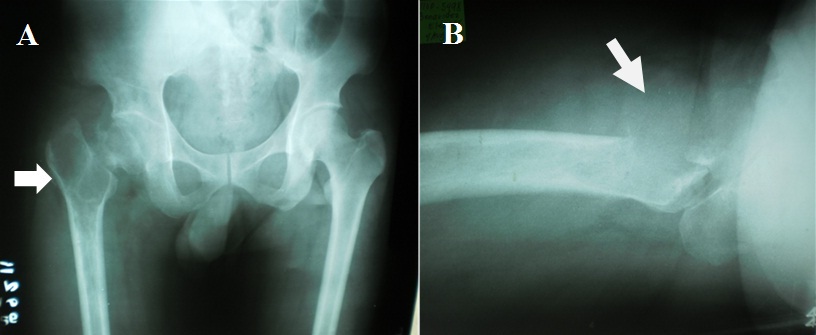

Two weeks prior to surgery, the patient’s pain increased in intensity up to a VAS score of 9/10. He did not recall any incident of fall or trauma. His limp worsened and was unable to put weight on his right lower extremity. He was eventually brought to our institution’s out-patient clinic. After initial assessment from the clinic’s triage, the patient was referred to our institution’s orthopedic and musculoskeletal tumor service. Physical examination done both by the orthopedic-musculoskeletal tumor specialist and orthopedic resident, indicated leg length shortening of 0.5 cm on the right lower extremity, right hip tenderness upon palpation, and a positive heel pound test. No skin lesions, palpable mass, nor lymphadenopathy were noted. The modified Musculoskeletal Tumor Society rating functional (MSTS) score was 4/30. Repeat plain radiographs of the hip revealed a pathologic fracture of the right femoral neck at the area of the lesion (Figure 1). The proximal femoral lesion was characterized as epi-metaphyseal, osteolytic with well demarcated borders, with endosteal expansion, cortical break, and has soft tissue extension anteriorly; but without any matrix. The lesion extended from the femoral neck up to the base of the lesser trochanter. The patient was admitted for further work-up and his right lower extremity was placed in skin traction. Magnetic resonance imaging of the hip confirmed a well delineated homogenous 8x7 cm lesion from the greater trochanter up to the level of the base of the lesser trochanter (Figure 2). A pre-operative tru-cut biopsy was done in the ward to exclude other differential diagnosis such as aneurysmal bone cyst and other primary bone tumor. The results confirmed giant cell tumor of the bone. The radiologic grade of the tumor was a Campanacci III due to the anterior cortical break and soft tissue extension, while the clinical and histologic grade was an Enneking 3 (for benign lesions). A pre-operative chest X-ray was done to rule out pulmonary metastasis, and showed negative results. The authors decided to pursue wide excision and perform total hip replacement due to the patient’s age and function, high recurrence for GTCb, along with the extensiveness of the lesion and the cortical break. Prosthesis specifications that were considered included a custom-made proximal femur endoprosthesis or a proximal femoral allograft composite. However, due to financial constraints and unavailability of a proximal femur allograft, a calcar-replacing femoral stem was selected due to the involvement and possible excision of the calcar femorale and lesser trochanter.

Figure 1: Plain radiographs of the hip revealing an osteolytic lesion with a pathologic fracture of the right femoral neck at the area of the lesion.

A) Arrow pointer showing proximal femoral lesion characterized as epi-metaphyseal, osteolytic with well demarcated borders, has endosteal expansion, cortical break, soft tissue extension, but without any matrix. The lesion extending from the femoral neck up to the lesser trochanter,

B) Arrow pointer showing cortical break at the anterior cortex of the greater trochanter and soft tissue extension of the tumor.